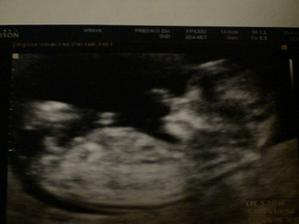

25.1.2010 NT screening 12tt+2 Všechno v pořádku🙂))))))))))) Nosní kůstka je. Šíjové projasnění 1,2mm🙂 super. Máme CRL 5,72cm. Pan doktor byl velmi spokojený. Screening krve NEGATIVNÍ 🙂))))))))

1.2.2010 KO 13tt+2 v pořádku, máme CRL 6,7cm.